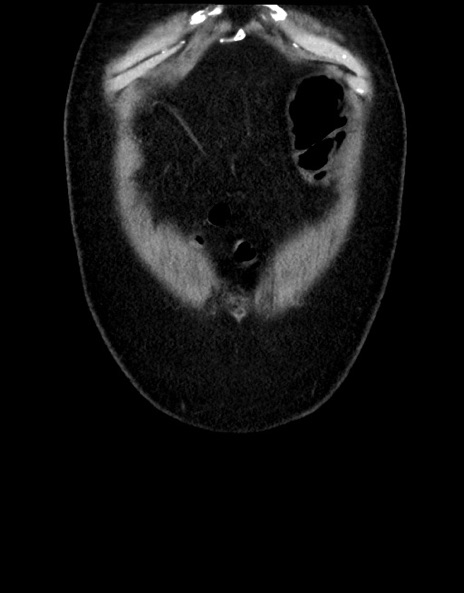

横断像